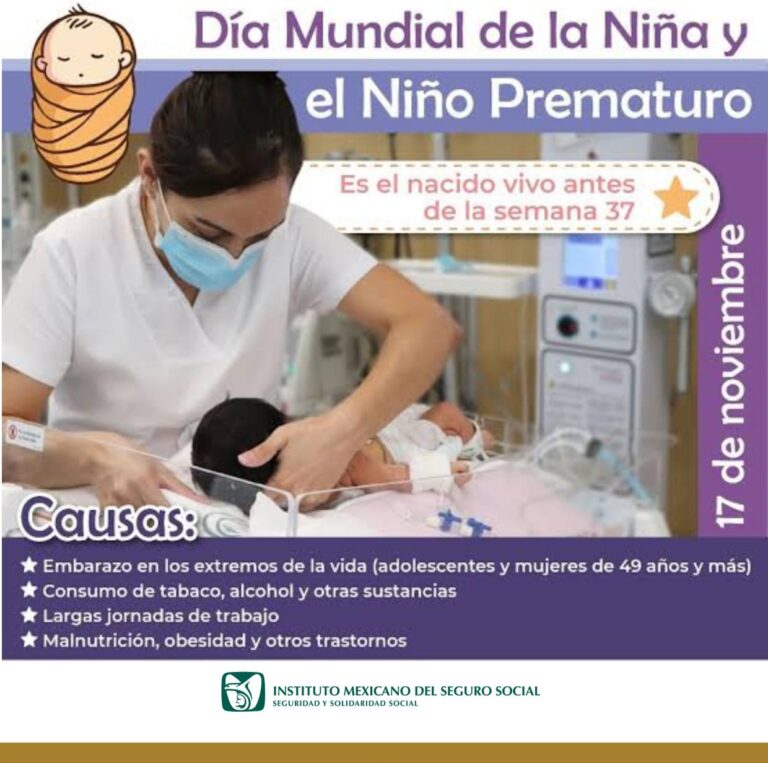

El Instituto Mexicano del Seguro Social (IMSS) en Veracruz Sur hace las siguientes recomendaciones,...